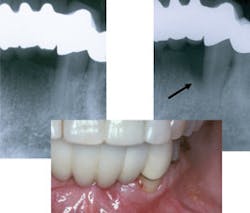

Periodontitis incidence is 71% in adults over age 65. The disease is inflammatory in nature, occurs as a response to a stimulus such as bacteria, and results in loss of collagen (Fig. 4). Oxidative tissue damage is involved in the pathogenesis of periodontal disease and is the result of excessive production of reactive oxygen species (ROS) by neutrophils. Recent clinical studies have shown a positive association between periodontitis and blood ROS levels. Nonsurgical periodontal treatment improved clinical parameters and reduced plasma ROS levels. Thus the addition of daily applied topical antioxidants can neutralize free radicals and reduce inflammation associated with periodontal disease.